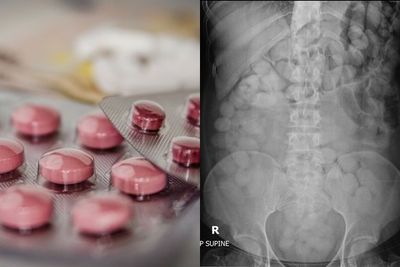

南韓一名男子日前鋌而走險做起人體運毒的生意,他先是吞入上百包用塑膠袋包裹的搖頭丸以及1包K他命,隨後從泰國搭機返國。然而他雖躲過海關,但僅僅1天後就被人發現陳屍家中,死因為搖頭丸急性中毒,當時他血液中的搖頭丸濃度高達每公升20.36毫克。法醫相驗後,竟在他的胃部發現79袋包裝破裂的搖頭丸。 《詳全文...》